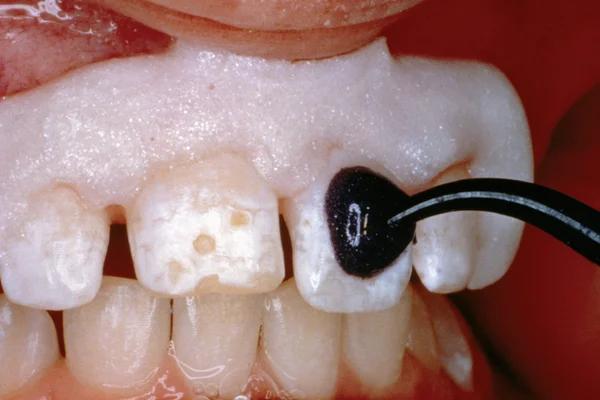

• Use XBW shade of G-aenial® Universal Injectable for easy differentiation between the tooth, composite material and the restoration.

6. Apply G-ænial Universal Injectable to the gingival margin of the proximal box.

7. Light cure

8. Remove the matrix and check for

covered with adhesive on the rest of the tooth with a fine grit diamond bur.

4. Apply a bonding agent (G-Premio BOND or G2-BOND Universal).